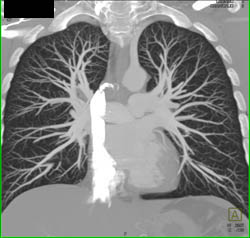

Dilated Sinus of Valsalva